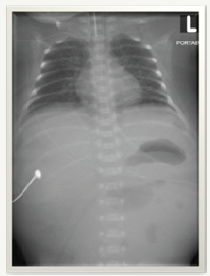

f) He was admitted to the NICU for management of prematurity and respiratory support (Figure 1).

Figure 1:

g) His initial chest x-ray was unremarkable. Started on IV Ampicillin and Gentamicin owing to high risk of infection but were discontinued after 48 hours as he remained well and sepsis screen was normal along with sterile blood culture.